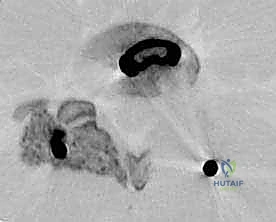

الخطوة 2: إزالة الضغط العصبي (Decompression)

يقوم د. هطيف بإزالة الأجزاء العظمية الضاغطة (Laminectomy أو Facetectomy) والأربطة المتضخمة بدقة ميكروسكوبية لتحرير الأعصاب الشوكية المختنقة.

الخطوة 3: استئصال القرص التالف (Discectomy)

يتم تفريغ القرص الغضروفي التالف بالكامل، وإعداد المساحة بين الفقرتين (Endplates) لاستقبال الطعم العظمي. هذه الخطوة حاسمة لضمان التحام العظام لاحقاً.